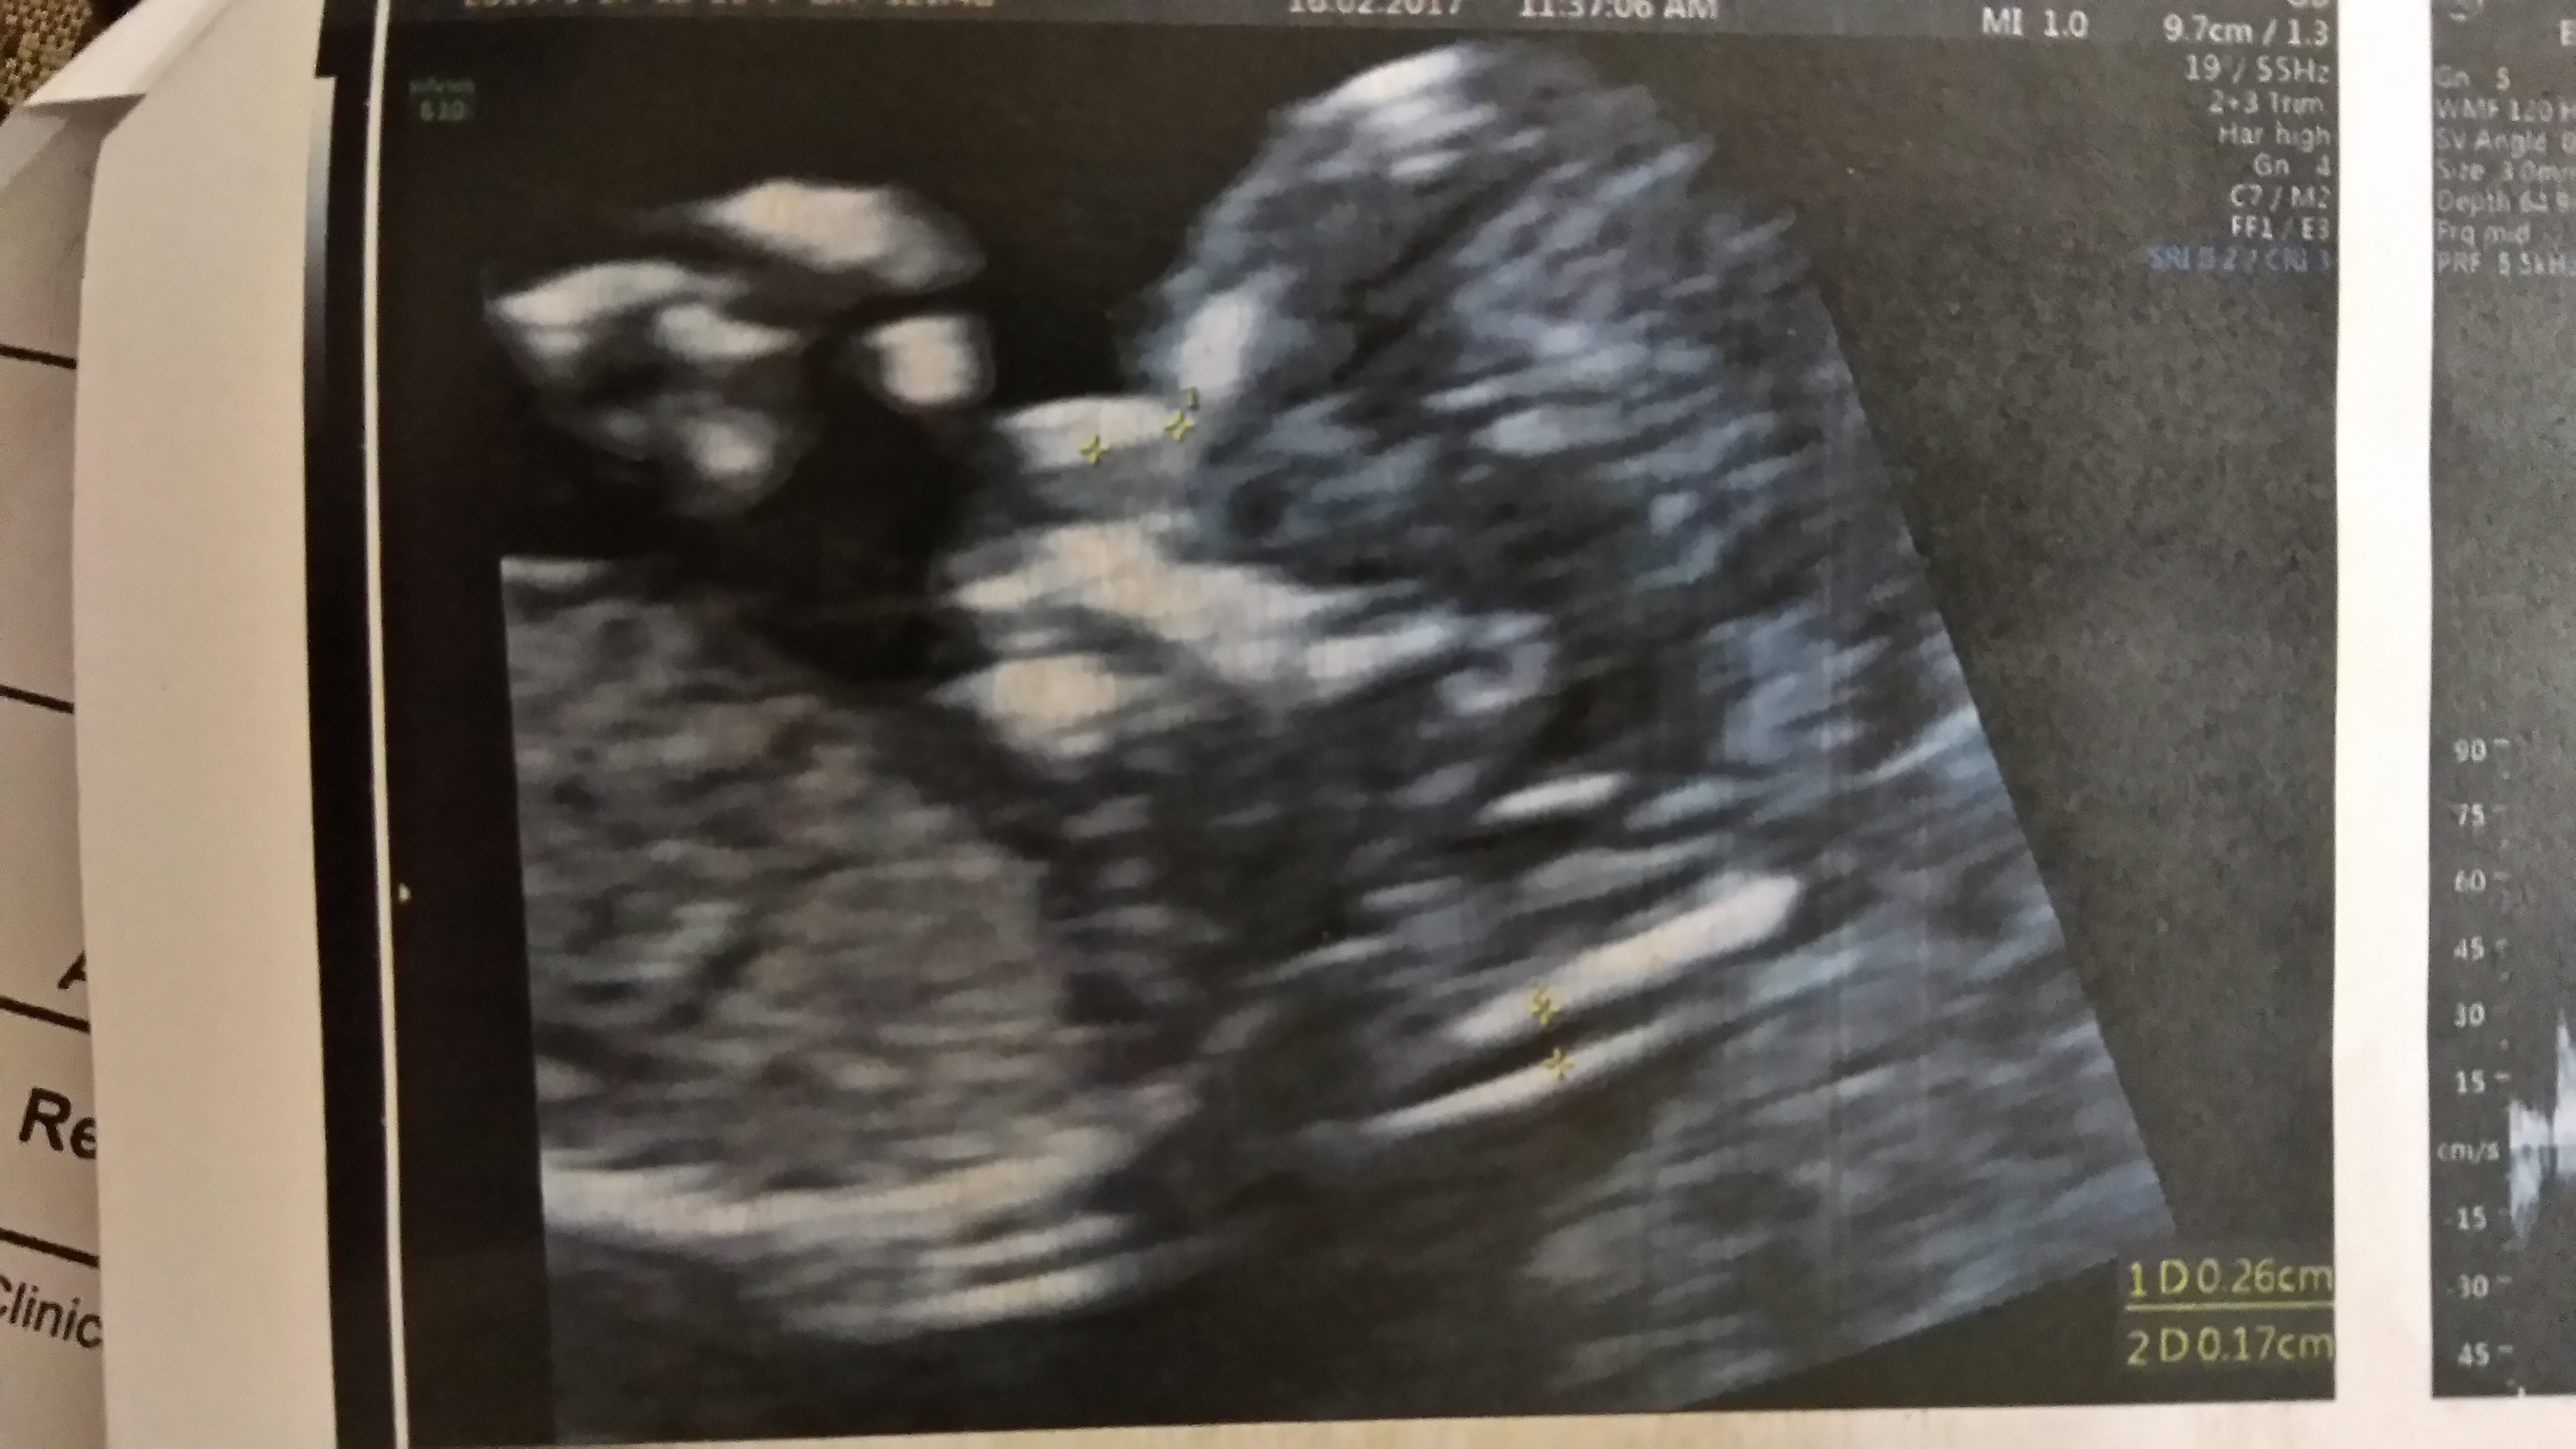

Boy skull, but not reliable!

NT is 1.7

Nasal length 2.7

HCG Mom: .44

Papp A Mom: 1.02

No clear nub shot